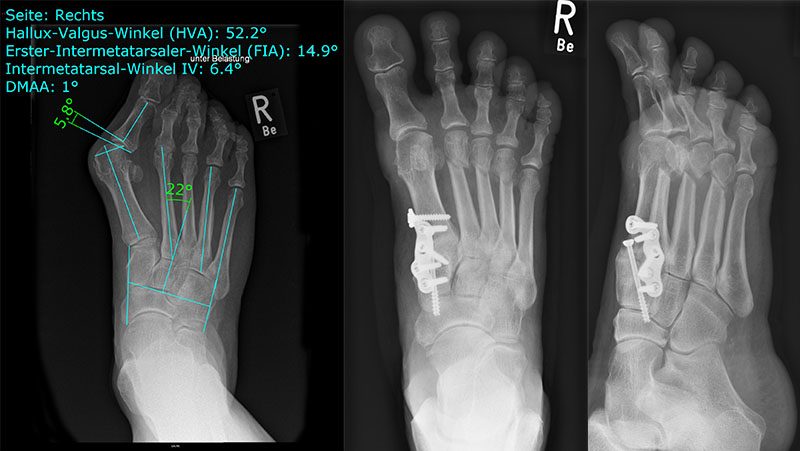

• Folgende Winkel können präoperativ zur Erleichterung der Planung am Röntgenbild eingezeichnet werden:

• IMW (Intermetatarsalwinkel).

• HVW (Hallux valgus-Winkel).

• DMAA (Distal Metatarsal Articular Angle) – Planung der ggf. notwendigen Reverdin-Isham-Osteotomie.

• PPAA (Proximal Phalangeal Articular Angle) – Planung der ggf. notwendigen Akin-Osteotomie.

• VAW (Vorfußadduktionswinkel) – Planung der Ausrichtung der DMMO (Distalen minimalinvasiven Metatarsale Osteotomien).

Einschränkend ist anzumerken, dass o.g. Winkel projektions- und rotationsabhängig sind 15. Daher ist intraoperativ die Planung anhand von Bildverstärkeraufnahmen zu verifizieren und ggf. anzupassen.

Zum Lesen der Bildbeschreibung und zur Vollansicht bitte das Bild anklicken.

In unserer prospektiven Studie wurden 10 Patienten (8 Frauen und 2 Männer; Ø Alter 58 ¼ Jahre) mit einem symptomatischen Hallux valgus bei Pes adductus und Metatarsalgie mittels einer Lapidusarthrodese und einer lateralisierenden DMMO versorgt. Die Fusion des TMT-I-Gelenkes erfolgte offen mittels einer winkelstabilen, plantaren Platte. Alle zusätzlichen distalen Eingriffe (DMMO, Isham-OT, Akin-OT, Kleinzehenkorrekturen) wurden in minimalinvasiver Technik durchgeführt. Die Patienten wurden nach 6 Monaten klinisch und radiologisch nachuntersucht.

Der präoperative AOFAS-Score betrug 41,5 Punkte und konnte postoperativ auf durchschnittlich 86,2 Punkte verbessert werden (p<0,005). Der IMW reduzierte sich von Ø 16,7° (8,5°-20,3°) präoperativ auf Ø 7,14° (6,1°-9,5°) (p<0,005). Ebenso konnte der HVW von präoperativ Ø 45,2° auf postoperativ Ø 9,4° (p<0,005) korrigiert werden. Durch die Durchführung der modifizierten, lateralisierenden DMMO veränderte sich der präoperative VAW von Ø 23° (19,3°-33,5°) auf Ø 15,6° (13°-17,2°; p<0,004).